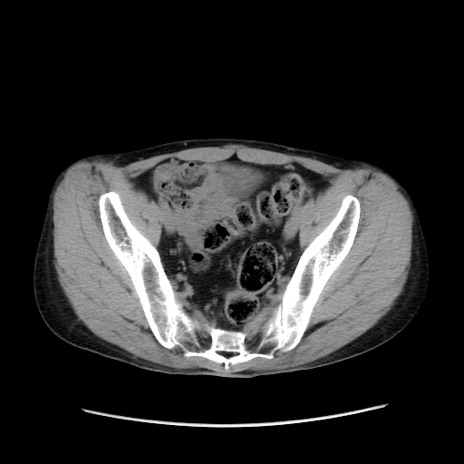

症例37(横断像)

【症例】40歳代 男性

【主訴】腹痛

【現病歴】4時間ほど前に電車に乗車中に臍部上より腹痛出現。徐々に増悪し起立困難となり、救急外来受診。生ものは数日食べていない。今朝お雑煮を食べた。

【身体所見】BT 36.8℃、BP 117/84mmHg、HR 91/min、SpO2 97%、苦悶様、腹部:臍上部広範囲圧痛あり、反跳痛±

【データ】WBC 8100、CRP 0.03